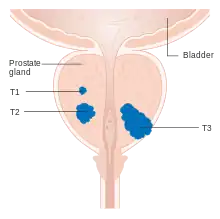

Staging

An important part of evaluating prostate cancer is determining the stage, or degree of spread. Knowing the stage helps define prognosis and is useful when selecting therapies. The most common system is the four-stage TNM system (abbreviated from tumor/nodes/metastases). Its components include the size of the tumor, the number of involved lymph nodes, and the presence of any other metastases.[94]

The most important distinction made by any staging system is whether the cancer is confined to the prostate. In the TNM system, clinical T1 and T2 cancers are found only in the prostate, while T3 and T4 cancers have metastasized. Several tests can be used to look for evidence of spread. Medical specialty professional organizations recommend against the use of PET scans, CT scans, or bone scans when a physician stages early prostate cancer with low risk for metastasis.[95] Those tests would be appropriate in cases such as when a CT scan evaluates spread within the pelvis, a bone scan looks for spread to the bones, and endorectal coil magnetic resonance imaging evaluates the prostatic capsule and the seminal vesicles. Bone scans should reveal osteoblastic appearance due to increased bone density in the areas of bone metastasis—the reverse of what is found in many other metastatic cancers.

After a biopsy, a pathologist examines the samples under a microscope. If cancer is present, the pathologist reports the grade of the tumor. The grade tells how much the tumor tissue differs from normal prostate tissue and suggests how fast the tumor is likely to grow. The pathologist assigns a Gleason number from 1 to 5 for the most common pattern observed under the microscope, then does the same for the second-most common pattern. The sum of these two numbers is the Gleason score. The Whitmore-Jewett stage is another method.